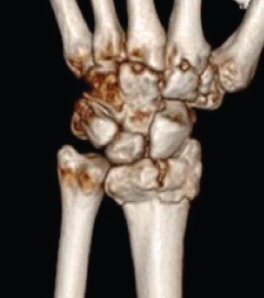

Aneurysmal Bone Cyst of Lateral Cuneiform: Challenge in Diagnosis and Management

Purushotham Lingaiah , A R Nataraj ………………………………p.233-237